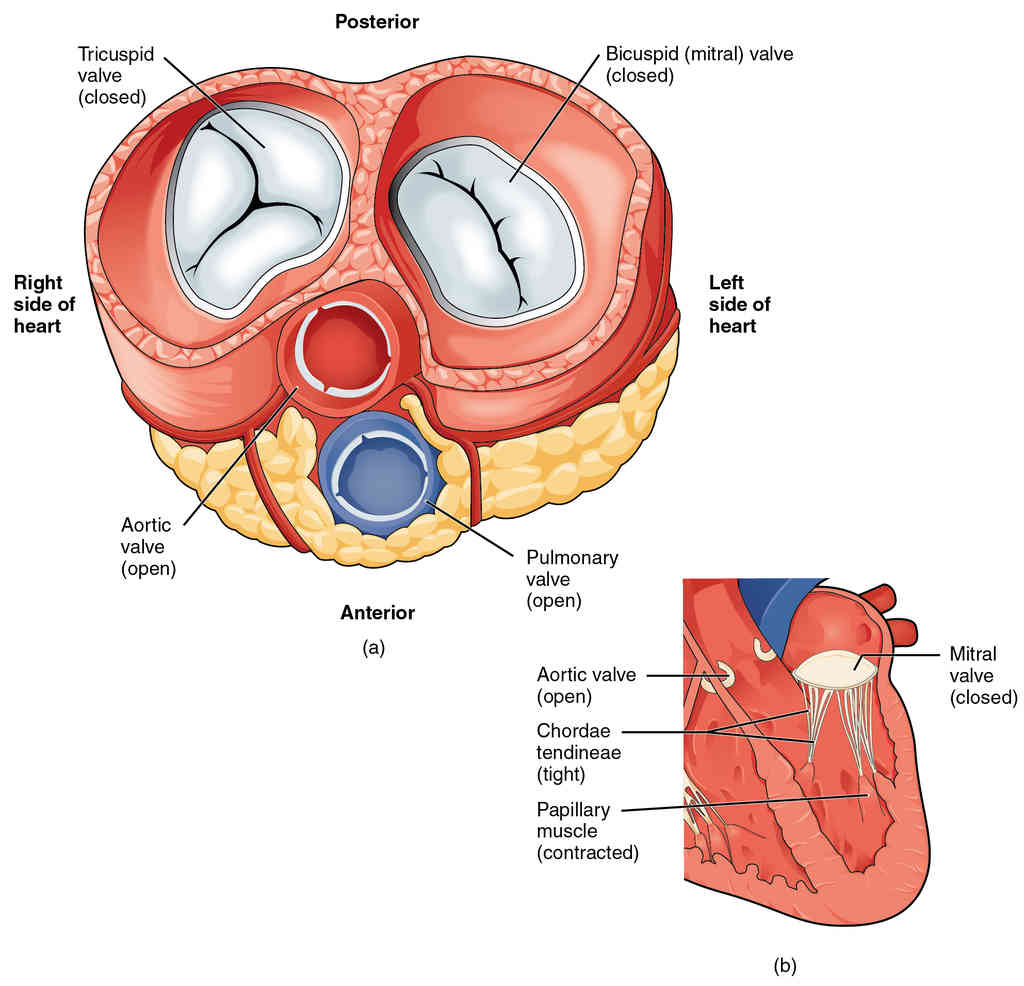

This page is under construction. For now, it is just a resource of the images found in the OpenStax Anatomy and Physiology Handbook. It wil slowly change into a revision tool. Each slide has a number. Use this to refer to the slide. When completed, it will have an unlabelled section, with labelled slides in parallel. On the unlabelled slides, write your answer and use the labelled slide to assess yourself. Keep track by also noting the number on each slide. Improvement at each attempt is important, more so than full marks on a first attempt.